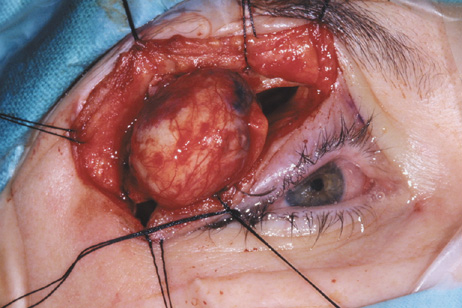

Fig. 6. Lateral orbitotomy through upper eyelid skin crease A. Photo demonstrating right globe ptosis present for more than 2 years. B. Axial CT scan showing a well outlined oval lesion in the lacrimal gland

fossa. C. Coronal CT showing lesion pushing globe inferiorly. D. Skin crease excision marked for lateral orbitotomy. E. Lateral orbital rim exposed. Bone cuts made above frontozygomatic suture

and at zygomatic arch. F. Lateral wall removed. Subperiosteal space exposed. Hard tumor could be

palpated in area of lacrimal gland. G. Benign mixed tumor of lacrimal gland removed. H. Bone sutured into place. I. Skin crease closed. |